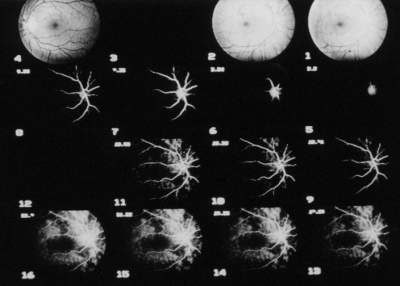

Unmittelbar nachdem die Aufnahme der FLADOP abgeschlossen ist, können die einzelnen Bilder des Angiogramms einer digitalen Bildverarbeitung zugeführt werden (Abb. 16) . Die Netzhautgefäße werden, soweit keine Trübungen der brechenden Medien vorliegen, angiographisch stets kontrastreich abgebildet. Da die Fluoreszenz der Aderhautgefäße durch die darüberliegenden Strukturen (Netzhaut mit Pigmentepithel und Choriokapillaris) sowohl absorbiert als auch gestreut wird, kommen diese nur unscharf zur Darstellung. | ||||||||||||||||||||||||||||||||||||||||

Abb. 16 Digitales Funduskamera-System DFC-512 (DFC-FLADOP): Darstellung des gesamten Angiogramms in 2 Sets von jeweils 16 Bildern